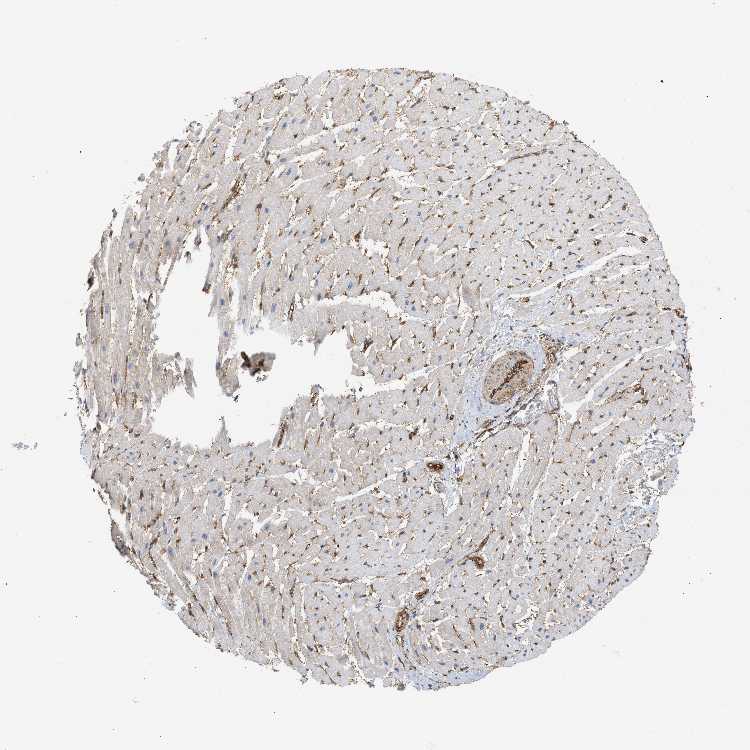

HEART MUSCLE - Antibody stainingi

Antibody staining in the annotated cell types in the current human tissue is reported as not detected, low, medium, or high, based on conventional immunohistochemistry profiling in selected tissues. This score is based on the combination of the staining intensity and fraction of stained cells.

Each image is clickable and will lead to virtual microscopy that enables deeper exploration of all samples and also displays staining intensity scores, fraction scores and subcellular localization as well as patient and tissue information for each sample.

Antibody HPA040736Antibody CAB018383Antibody CAB018737

Cardiomyocytes LowLowHigh